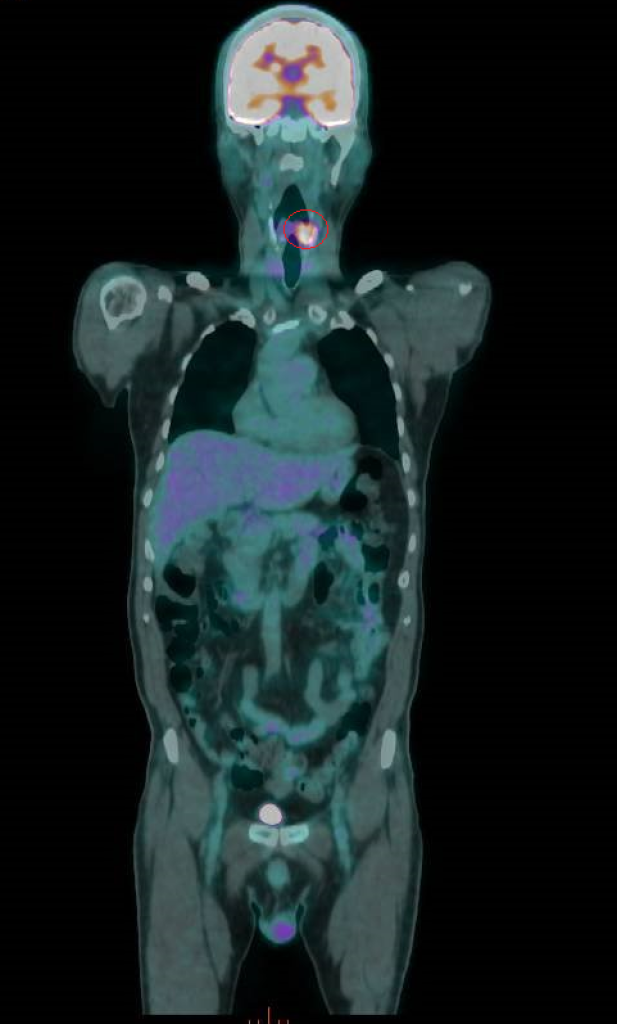

菸檳酒惹的禍 56歲男下咽癌復發「切全喉」求生

56歲的曾先生抽菸、嚼檳榔、喝酒超過30年,3年前發現下咽癌,經放射線及化學治療後,腫瘤消失,他也戒掉菸、檳、酒,沒想到在以為已熬過難關的第3年,癌症復發,最終接受全喉切除手術,失去聲帶,靠人工發聲器重新說話。-